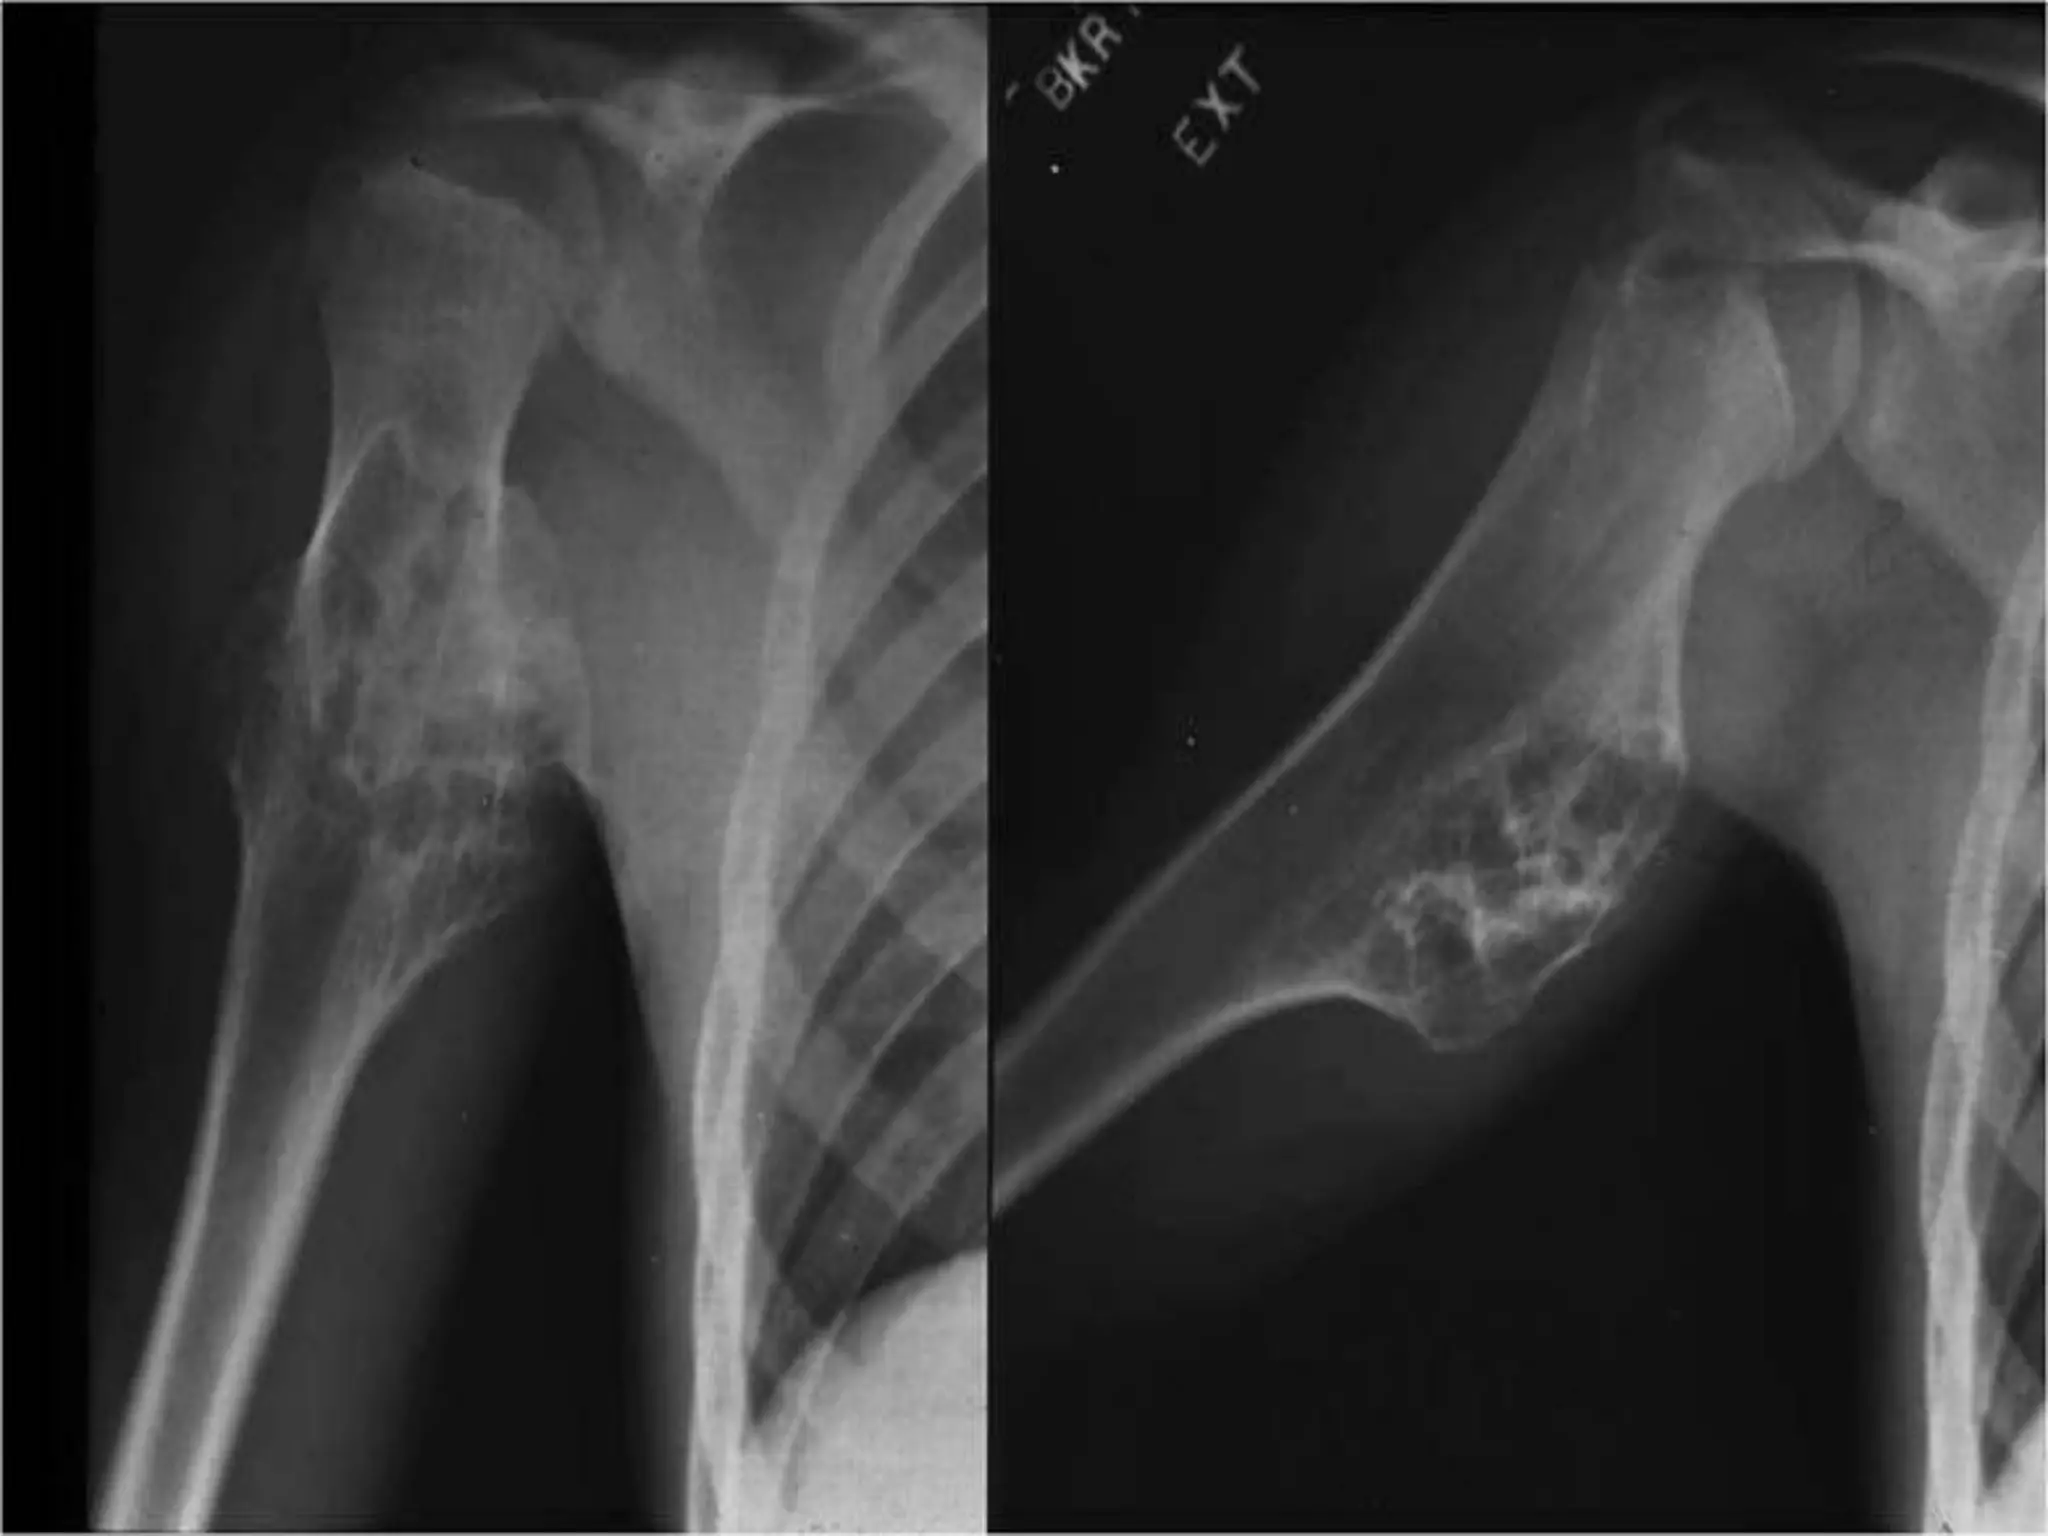

• A 55 years old lady complains of acute pain in the

left shoulder region for last 3 weeks.

• The pain is diffuse over the upper end of arm,

relentless and not relieved by analgesics

prescribed by the local doctor. There is no bony

swelling in the painful area. She gives a history of

receiving chemotherapy 3 years back. Bone scan

shows increased uptake at the left proximal

humerus. X-ray shows a lytic lesion in the

proximal humerus. There is also erosion of

cortex.

Radiological Findings

 hazy osteolytic areas which may alternate with unusually dense

osteoblastic areas.

 Area of irregular destruction in metaphysis, sometimes

overshadowed by new bone formation

 Erosion of cortex overlying lesion

 There may be also a poorly define endosteal margin.

 Periosteal reaction : Tumor lifts the periosteum which is

irregular , smooth layer in OM

 Codman’s triangle: Reactive new bone formation at the angles

of periosteal elevation.

 Sun- ray appearance/Sunburst effect: Growing tumor grows into

the overlying soft tissues, bone laid down along blood vessels

within tumor growing centrifugally

Chest X ray: to detect lung metastasis.